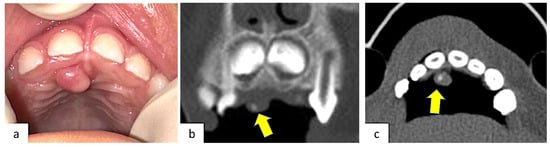

2. Case Presentation

| 10 | Friedrich et al. [2] (2010) | Male/3 years | Maxilla, palatal region | Unspecified | Peripheral developing odontoma | Excisional biopsy |

| 19 | This study (2023) | Male/4 years | Maxilla, palatal region | Peripheral ossifying fibroma | Peripheral developing odontoma | Surgical laser excision |